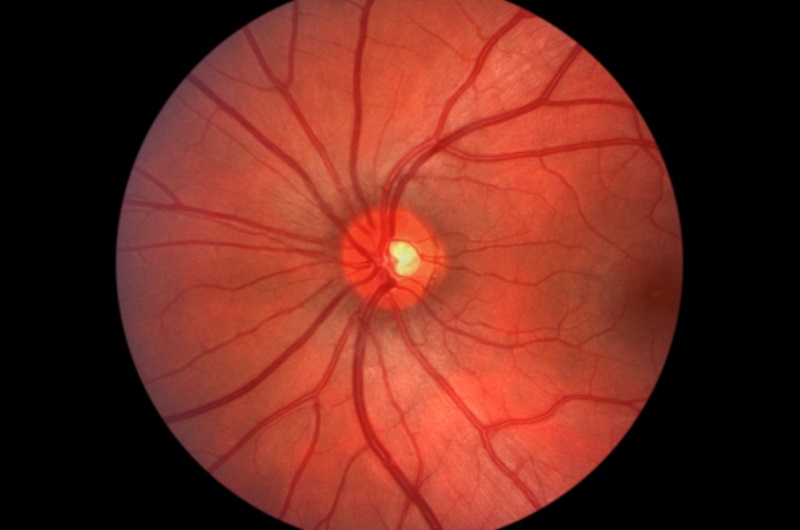

Digital Retina Imaging

Using a digital camera system, our optometrists can clearly see and examine your retina, located at the back of your eye. This examination is critical to monitoring the health of your eye as well as to the early detection of many medical problems. The pictures generated through retinal imaging help us identify problems with your vision and can also help diagnose other medical conditions such as high blood pressure, diabetes, cholesterol, or even brain tumors.